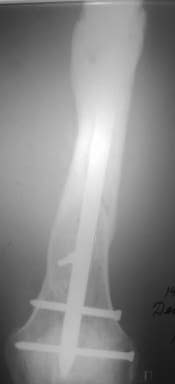

Уважаемые коллеги! На консультации больной предъявляет жалобы на хромоту (укорочение - 2см), боль в месте перелома при нагрузке (спортсмен).

Семь месяцев назад получил закрытый перелом, лечился консервативно в одной из больниц города. Как-бы кто лечил? Сам склоняюсь к LCP с костной пластикой.

При невозможности или чрезмерной травматичности одномоментного восстановления длины можно пойти двухэтапно (аппарат, потом гвоздь). Похожий пример см. тут. Прошло уже года полтора после остеосинтеза. Может, коллега Зырянов покажет годичный результат, если есть?

Александр Николаевич, к сожалению больной не является на контрольные осмотры. Я последний раз видел больного, когда прошло 7 месяцев после операции БОС. У него все хорошо. Каких либо жалоб и ограничений в нагрузке нет. Высылаю снимки до операции и последние снимки.